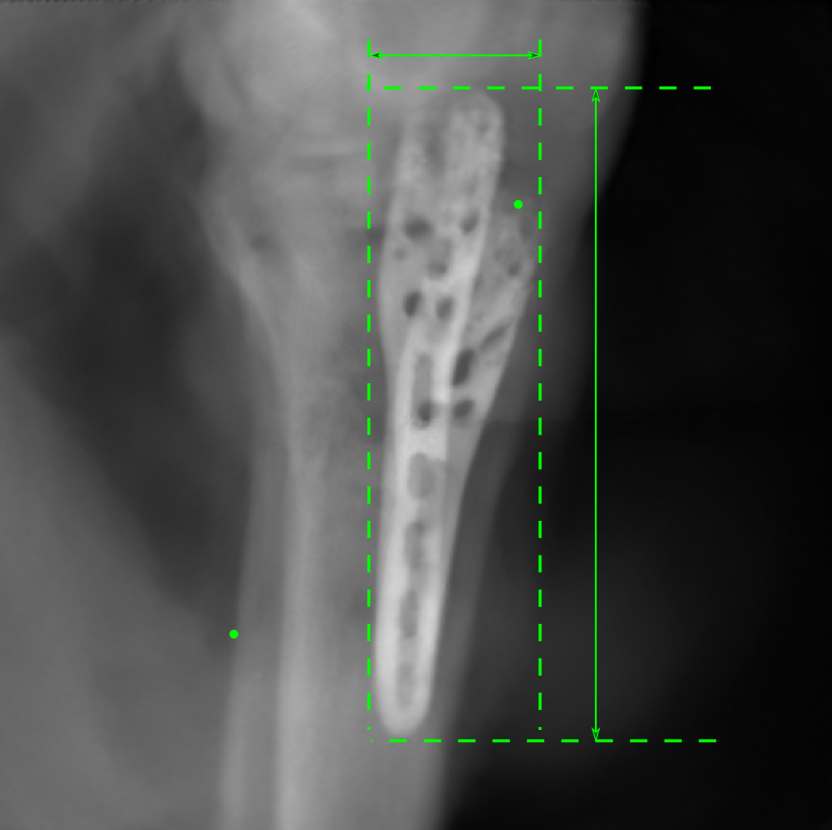

5.4 Real Knee Data with Metal Implants

Refer to caption

Figure 13: Three examples of synthetic perspective projection images for training, intensity window: [0, 4]. The appearance (e.g., image contrast and metal image resolution) of such DRR training images is different from that of real projection images in Fig. 14.

0superscript00^{\circ} perspective

[Uncaptioned image]

(a) 32.56, 109.85

(b) 18.91, 19.54

180superscript180180^{\circ} perspective

(c) 28.11, 112.16

(d) 15.80, 19.27

View difference

0superscript00^{\circ} and 180superscript180180^{\circ} RGB

DRR reference

(e) 29.72, 111.80

(f) 17.14, 19.38

Pix2pixGAN

(g) 29.72, 111.80

(h) 17.50, 19.70

(Fig. 14 continues in the next column.)

TransU-Net

(i) 29.72, 111.80

(j) 16.23, 19.25

Figure 14: The results for the real cadaver leg data. The green dots mark the positions of landmarks in the corresponding reference images. In the first column, the arrows indicate the bone cavity/fracture structures. In the second column, the solid lines mark the widths and heights of the metals. The green ones are measured from the DRR reference, while the red ones are measured in the corresponding perspective projection image. In the last column, the lines mark the centerlines of the metal screws, where the green lines are those from the reference image. The lengths of the lines in mm are displayed in their corresponding subcaptions. Intensity window: [0, 4]. Please zoom in for better visualization.

The complementary view setting for learning perspective deformation is also evaluated on real CBCT projection data. In this evaluation, real CBCT projection data from a dataset of knees with metal implants is used for testing, while DRRs created from volumetric CT datasets with inserted metals is used for training. Three exemplary DRR perspective projection images for training are displayed in Fig. 13, in which synthetic metal implants are inserted [34]. The appearance, e.g., image contrast and metal image resolution, of such DRR training images is different from that of real projection images in Fig. 14. In Fig. 14, the results for three knees, with and without metal implants, are displayed. The first and second rows are the 0superscript00^{\circ} and 180superscript180180^{\circ} perspective projections, respectively, rebinned to the virtual detector with geometric calibration based on their respective principal points and projections of the world origin. The third row displays their difference images, where the magnitude of deviation increases from the center towards the outside like it does in DRRs with an ideal scan trajectory (e.g., Fig. 6(e)), although real projection data suffer from various physical effects like beam hardening and Poisson noise. The fourth row displays the RGB stacks of 0superscript00^{\circ} and 180superscript180180^{\circ} perspective projection images. The magenta and green regions indicate structures with considerable perspective deformation, for example, the knee patella in Fig. 5.4, the top parts of the two metals in Fig. 5.4, and the bottom two screws in Fig. 5.4. The fifth row displays reference images, which are orthogonal projections of iterative reconstruction volumes from measured CBCT projection data. In the reference images, a total of five landmarks are selected, with the positions being marked by the green dots: In Fig. 5.4, two positions at the edges of the knee patella are marked; In Fig. 14(e) and Fig. 14(f), one position at the left edge of the fibula is marked for each image. In addition, a rectangular frame for the two metals is marked by the green dashed lines, while its width and height are indicated by the green solid lines, which are 29.71 mm and 111.99 mm, respectively. In Fig. 14(f), the centerlines of the bottom two screws are sketched by the green lines, which have the lengths of 17.14 mm (middle screw) and 19.38 mm (bottom screw). The corresponding rectangular frame for the two metals and the screw centerlines in the perspective projection images are marked as well, but in red color. In Fig. 14(a), the width and height of the metals are 32.56 mm and 109.85 mm, which have deviations of 2.84 mm and -1.95 mm to the reference ones, respectively. In Fig. 14(b), the centerline lengths are 18.91 mm and 19.54 mm, which have deviations of 1.77 mm and 0.16 mm, respectively. Although the bottom screw has little length deviation to the reference, the orientations of both screws are obviously deviated. The sixth row shows the results of Pix2pixGAN using 0superscript00^{\circ} and 180superscript180180^{\circ} polar inputs. For all of the landmarks, the green reference dots are all located accurately in the Pix2pixGAN images. The rectangular reference frame also accurately covers the metals in Fig. 14(g). In Fig. 14(h), although the two red centerlines do not exactly overlap with the green one, they are very close in lengths and orientations. Please zoom in for better visualization.